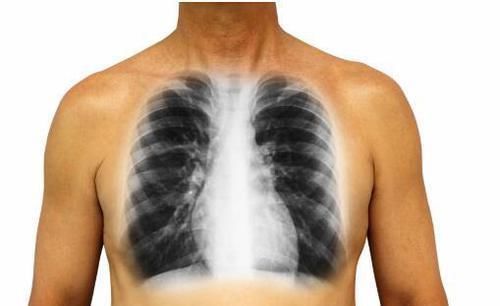

1、肿块:肿块是因为癌细胞恶性繁殖导致的,可以用手在自己皮肤表面或者是深一点的地方就可以摸到的。甲状腺、腮腺、乳腺等地方的癌症可以在皮下比较浅的地方触摸到肿块的。肿瘤如果转移到了淋巴结的话,那么患者还会出现淋巴结肿大的情况,有些表浅淋巴结,比如脖子的淋巴结和腋窝的淋巴结都是很容易摸到的。